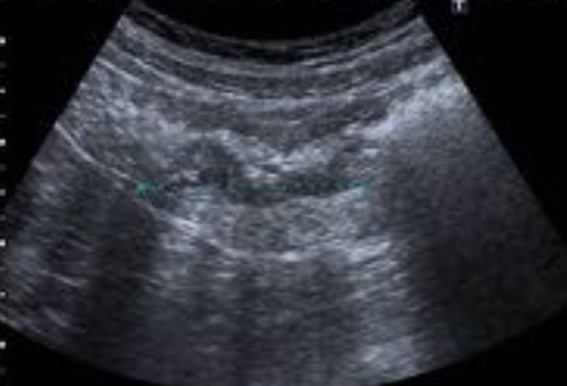

Ante la sospecha de cólico nefrítico complicado, se realiza ecografía abdominal, que muestra en fosa ilíaca izquierda, un foco ecogénico con sombra acústica posterior y engrosamiento de la pared intestinal de 6 mm. Se confirma mediante tomografía computarizada la presencia de divertículos en el colon izquierdo, con un divertículo engrosado entre el colon descendente y sigma, y discretos cambios inflamatorios pericólicos. Con mínimo líquido en la gotiera adyacente, sin colecciones ni burbujas de gas extraluminal.

Este caso subraya la importancia de una anamnesis completa y exploración física, que aunque no definitivas, ayudan a orientar el diagnóstico diferencial. Aunque diagnósticos comunes como el cólico nefrítico son frecuentes, es crucial no descartar otras patologías que podrían complicarse sin tratamiento adecuado. La ecografía, como herramienta inicial, permitió detectar signos de diverticulitis aguda no complicada, orientando el diagnóstico y tratamiento. Complementada por la tomografía computarizada, la ecografía demostró ser útil en el dolor abdominal localizado, destacando la importancia de un diagnóstico integral y el uso adecuado de herramientas disponibles.